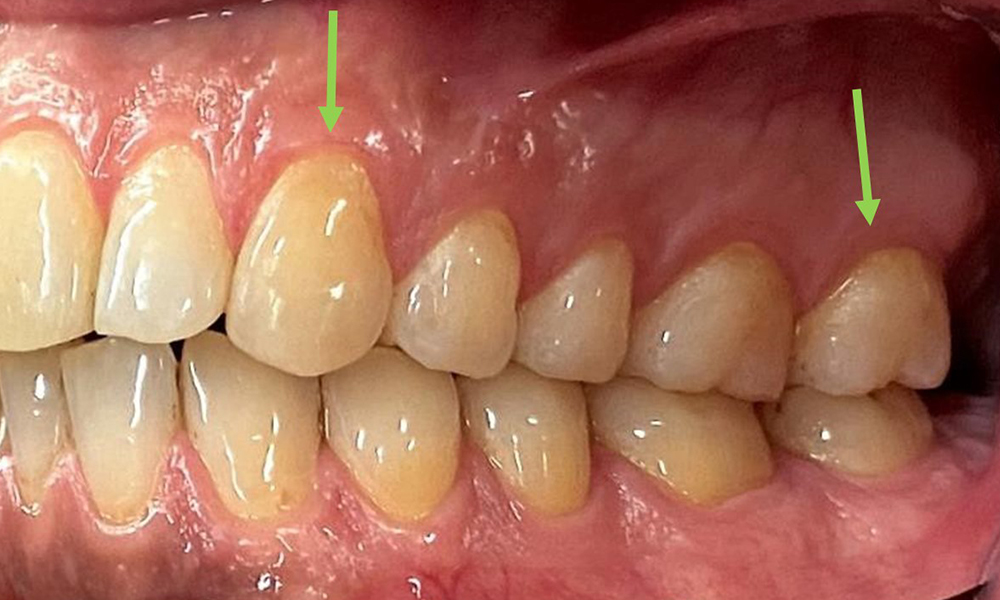

Няма патологични екстраорални резултати. По време на интраоралния преглед се установи кафеникаво оцветяване в близост до кератинизираната гингива и при прехода към подвижната лигавица (фиг. 2), което може да се отдаде на консумацията на никотин. В областта на небцето, особено в близост до небцовите повърхности на максиларните молари, се наблюдават белезникави лезии на лигавицата, които показват повишена кератинизация и също могат да се припишат на консумацията на никотин. Езикът е покрит с бяло-кафеникаво покритие, което може да се отстрани.

Пациентът има пълно съзъбие с общо 28 зъба. Налице са забележими ерозии и атриции. (Фиг. 4, Фиг. 5). Поради бруксизъм пациентът е носил шина с коригиран блок на захапката през нощта в продължение на много години. Ерозиите са причинени от продължителна консумация на изотонични напитки. Не сe наблюдава загуба на пародонтална кост или активни кариозни лезии.